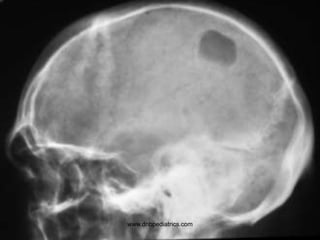

www.dnbpediatrics.com

Questions

• Describe the lesion?

• Give two D/D

• Osteolytic lesion of skull

• Histiocytosis

Metastasis

• Hyperuricemia, hyperkalemia, and

hyperphosphatemia

• Give atleast two D/D